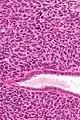

| Micrograph of a uterine adenosarcoma showing a mitotically active malignant stroma and benign glands. H&E stain. | |

Uterine adenosarcoma have, by definition, a malignant stroma and benign glandular elements. The World Health Organization (WHO) criteria have a mitotic rate cut point; however, this is often disregarded, as bland-appearing tumours with a low mitotic rate are known to metastasize occasionally.[2]